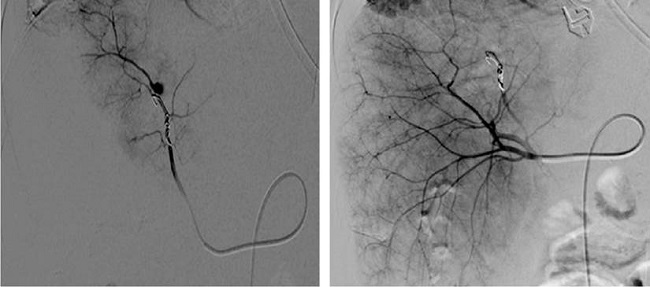

Se procedió entonces a la embolización del aneurisma (Figura 2), con lo cual el paciente evolucionó favorablemente, sin más episodios de sangrado digestivo y con la resolución completa de la obstrucción biliar.